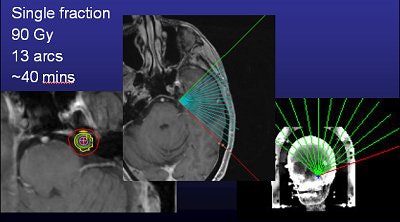

![]() |

| Above, frameless radiosurgery for TN. Below, three months after treatment. Images courtesy of Dr. Kevin Murphy and the University of California, San Diego, department of radiation oncology. |

Murphy and colleagues at UCSD work with a linac system (Trilogy) and also perform gamma knife surgery. Time is one major difference between the two options in TN. A procedure with the Trilogy system takes about 30 to 40 minutes versus about two to three hours with the gamma knife, he said.

UCSD started treating TN with the Trilogy system about a year ago, performing one to two procedures on a monthly basis. Initially, they reserved linac-based surgery for TN patients when other surgeries had failed, he said.

"We treated three patients who didn't want further gamma knife procedures with the bolted headframe. So far, all three are pain-free and they're very happy. Usually in a week to a month their pain goes away," he said.